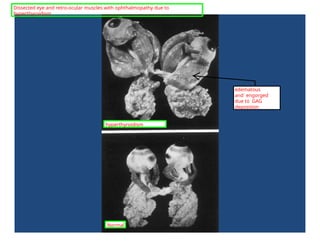

Panels A and B: pre treatment

Panels C and D: post

treatment

More ophthalmopathy due to

hyperthyroidism.

edematous

and engorged

due to GAG

Dissected eye and retro-ocular muscles with ophthalmopathy due to

Normal

hyperthyroidism